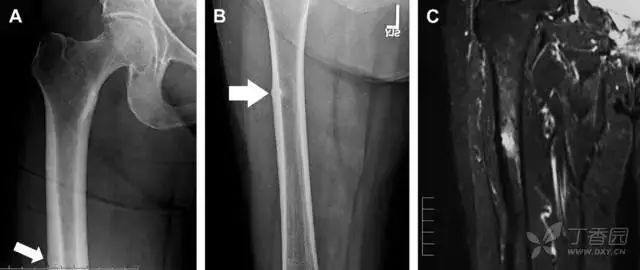

07非典型股骨骨折

另一种易漏诊的骨折是非典型股骨骨折,这种骨折与长期服用双膦酸盐相关,常发生在使用双膦酸盐 3 年以上的患者。前驱症状表现为腹股沟痛或大腿痛的患者中,60%~70% 被错误地认为由腰背痛或髋关节炎引起。

这种骨折的一个典型表现为火山口状骨膜隆起及一横行透亮带。值得注意的是,超过 50% 的患者表现为股骨干完全骨折。由于 50%~60% 的患者会累及双侧,所以一旦一侧下肢确诊,需行对侧下肢检查。

图 10 老年患者长期服用双磷酸盐引起的骨折。A 髋部正位片,箭头所示,股骨外侧皮质存在横行透亮带。B 后续的股骨 X 线片示局灶性骨膜反应,以及此类骨折的特征性表现-火山口状骨膜隆起(箭头)。C MRI 冠状位 STIR 序列扫描示相应骨折平面的骨髓水肿表现